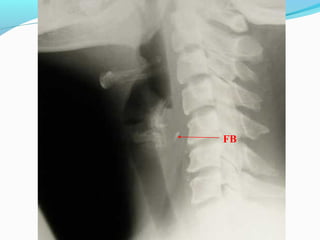

FB Throat - Investigations

Lateral neck XR

FB

Hyoid bone

Thyroid cartilage

Cricoid cartilage